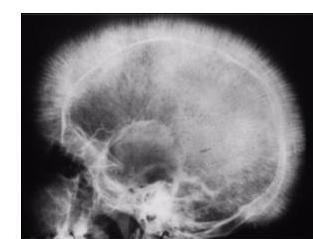

# ANEMIAS HEMOLÍTICAS ## DEFINICIÓN Se denomina hemólisis a la destrucción de hematíes; si la destrucción de hematíes es superior a la velocidad de regeneración medular, sobrevendrá una anemia. Fármacos Relacionados: CEFTRIAXONA. ## CLASIFICACIÓN Según la causa de la anemia hemolítica corresponda a un defecto propio del hematíe o a una acción externa del mismo, las anemias se clasifican en: - Anemias Hemolíticas Intracorpusculares (Hereditarias) - Anemias Hemolíticas Extracorpusculares (Adquiridas, excepto la Hemoglobinuria Paroxística Nocturna). Hemólisis Intravascular: aquella donde la destrucción de hematíes ocurre fundamentalmente en el aparato circulatorio. Hemólisis Extravascular: La que tiene lugar predominantemente en el bazo. ## ETIOLOGÍA 1. Destrucción de hematíe 2. Incremento de DHL sérica 3. Incremento de Bilirrubina Indirecta en suero 4. Disminución de HAPTOGLOBINA (proteína que se une a la hemoglobina) 5. Si hay hemoglobinuria se traduce a una hemolisis de predominio intravascular ## CLINICA TRIADA CARACTERÍSTICA ANEMIA ICTERICIA ESPLENOMEGALIA # ANEMIAS HEMOLÍTICAS CONGÉNITAS Existen tres tipos: 1. Defectos de la membrana del hematíe 2. Enzimopatías o trastornos del metabolismo del hematíe 3. Defectos de la hemoglobina ## DEFECTOS DE LA MEMBRANA DEL HEMATíE La membrana del hematíe tiene una capa de lípidos externa, que tiene como finalidad el aislamiento del hematíe e impedir la permeabilidad excesiva al agua. Por dentro hay un citoesqueleto de proteínas, la más importante ESPECTRINA. 1. Esferocitosis Hereditaria (Enfermedad de Minkowski-Chaufard) 2. Eliptocitosis Hereditaria 3. Estomatocitosis Hereditaria 4. Xerocitosis ## ESFEROCITOSIS HEREDITARIA Es la Anemia Hemolítica Congénita más frecuente. Trastorno de proteínas de la membrana (ANKIRINA 50%) Se PIERDEN FOSFOLÍPIDOS DE LA MEMBRA, se hace permeable y se hincha Se forman los esferocitos y llegan a los sinusoides esplénicos en donde se destruyen. - Clínica: Ictericia y Esplenomegalia + Anemia. (en situaciones se puede agravar la hemolisis, como infecciones) - Diagnóstico: DHL elevado, BI elevada, Reticulocitos elevados en SP / Prueba de Fragilidad Osmótica - Los esferocitos no son patognomónicos (pero es característico que presenten aumento de la CHCM y VCM normal) - Tratamiento: ESPLENECTOMÍA (retrasar hasta los 5-6 años) previa vacunación Neumococo y H. inluenzae. - No es curativa pero disminuye hemolisis. ## ELIPTOCITOSIS HEREDITARIA - Trastorno autosómico dominante - Habitualmente no produce manifestaciones cínicas - Defecto de la ESPECTRINA - ocasiona forma ELÍPTICA anormal del hematíe (no hay fragilidad osmótica) ## ESTOMATOCITOSIS HEREDITARIA Parecido a la esferocitosis hereditaria, pero mucho menos frecuente También hay defecto de la ESPECTRINA y en la permeabilidad de membrana Los hematíes se destruyen en el bazo. - Hidrocitosis: los hematíes están turgentes con exceso de iones y agua por lo que disminuye la HCM. - Rh Cero: los hematíes no expresan proteínas del sistema Rh, tienen forma de Estomatocito su vida media está acortada. XEROCITOSIS Hemolisis en donde hay deshidratación del hematíe por pérdida de K y Agua. La hemolisis ocurre por traumatismos repetidos. # ENZIMOPATÍAS O TRASTORNOS DEL METABOLISMO ## TRASTORNOS DE LA VÍA HEXOSA-MONOFOSFATO La causa más frecuente de Anemia Hemolítica Enzimopática es la DEFICIENCIA DE GLUCOSA-6-FOSFATO DESHIDROGENASA y se transmite de por herencia ligada al cromosoma X. Etiología: el ciclo de las hexosas-monofosfatos genera NADPH para reducir el glutatión. La oxidación de los grupos sulhidrilos produce metahemoglobina, precipitando en el interior del hematíe ocasionando los cuerpos de Heniz. Clínica: Muy variable, desde asintomáticos hasta Hemólisis Neonatal grave. Se puede producir crisis hemolítica por infecciones, acidosis, fiebre, inahlación de polen de habas, nitrofurantoín, sulfamidas, etc. Diagnóstico: Dosificación enzimática en el hematíe. NO debe ser en sangre muy rica en reticulocitos (o sea NO en las crisis hemolíticas) porque estos presentan hematíes con mayor cantidad de Gluc-6-fosfato Tratamiento: Evitar conductas que predispongan la crisis + Ácido Fólico. ## TRASTORNOS DE LA VÍA GLUCOLÍTICA (VÍA DE EMBDEN-MEYERHOF) - Consiste en una DEFICIENCIA DE LA PIRUVATO-QUINASA, siendo la causa más frecuente de la vía glucolítica. - Mucho menos común que la anterior (relación 10:1). - Transmisión autosómica recesiva. ## TRASTORNOS DEL METABOLISMO DE LOS NUCLEÓTIDOS Deficiencia de Pirimidina-5'-nucleotidasa: ausencia de esta evita la destrucción del ARN degenerada, ocasionando una precipitación del mismo, dando lugar a un PUNTEADO BASÓFILO, similar al saturnismo (plomo) Exceso de Enzima Eritrocitaria Deaminasa de Adenosina: Ocasiona disminución de formación de ATP en el hematíe. # DEFECTOS DE LA HEMOGLOBINA La hemoglobina normal está constituida por 4 CADENAS GLOBINA + 4 NÚCLEOS DE HEMO. En el hematíe del adulto, 97 % de la hemoglobina está formada por Hemoglboina A, formada por 2 cadenas Alfa y 2 Beta; un 2% está formada por Hemoglobina A2 y 1% está formado por Hemoglobina Fetal F. Los genes de la cadena Alfa se encuentran en el cromosoma 16 y el resto en el 11. Herencia autosómica recesiva. Existen 2 tipos de defectos de la hemoglobina: Defecto de la síntesis de cadenas de globina (TALASEMIAS) Formación anómala de cadenas de globina (Hemoglobinopatías) ## TALASEMIAS (Defectos de la Síntesis de Globina) La disminución de síntesis de cadenas Beta (Beta-Talasemias) es más frecuente en el área mediterránea, oriente próximo y África. Mientras que las cadenas Alfa (Alfa-Talasemias) son frecuentes en Asia. El defecto hemolítico es provocado por el EXCESO DE CADENA DE GLOBINA que se sintetiza normalmente, que al no poder unirse a la cadena de globina que se sintetiza defectuosamente, precipita en el interior del hematíe, ocasionando lesión y hemolisis, además de eritropoyesis ineficaz. ## BETA-TALAESEMIAS: - LA ANEMIA HEMOLÍTICA MÁS COMÚN EN MÉXICO. Según la gravedad de la clínica se pueden agrupar en dos presentaciones (clínica aparece 6 - 8 meses de vida): ## TALASEMIA MAJOR (Anemia de Cooley o Talasemia Homocigota) La gran disminución se cadenas B ocasiona descenso importante de síntesis de Hemoglobina A, aumenta la formación de hemoglobina A2 y Hemoglobina F. 1. La grave anemia aumenta la Eritropoyetina - Hiperplasia de M.I - Malformaciones óseas: - Pseuodiquistes en manos y pies - Deformidad de cráneo (Cráneo en Cepillo) - Neumatización de los senos paranasales  2. Hemosiderosis Secundaria: La disminución de cadena B también produce aumento de Hemoglobina F que presenta mayor afinidad por el oxígeno - cesión defectuosa a los tejidos - hipoxia tisular crónica. - hiperplasia medular - aumento de absorción de hierro. 3. Organomegalia por hematopoyesis extramedular . Diagnóstico: ELECTROFORESIS DE HEMOGLOBINA (objetiva descenso de Hb A y aumento de HbA2 y HbF). ## TALASEMIA MINOR O RASGO TALASÉMICO (Heterocigotos Simples) - En estos casos prácticamente no presentan anemia ni sintomas - Es la variante más frecuente. - SOSPECHAR EN MICROCITOSIS importante con numero normal o incrementado de hematíes - Cribado - VCM e Indice Corpuscular Medio - Puede detectarse ligero aumento de Hemoglobina A. # HEMOGLOBINOPATÍAS (Defectos Estructurales de la Hemoglobina) Son trastornos genéticos en los que por mutación se ocasiona una formación de cadenas anormales de globina, que tiene una función defectuosa de transporte de oxígeno y habitualmente precipitan en el interior del hematíe, ocasionando su destrucción. HEMOGLOBINOPATÍA S (Anemia de Células Falciformes o Drepanocitosis) Sustitución en la cadena Beta de Ácido Glutámico en la posición 6 por una molécula de VALINA. Gravedad clínica variable. Cuando la Hemoglobina S pierde oxígeno, se precipita en el interior del hematíe, adoptando una MORFOLOGÍA DE HOZ (Falciforme). - DOLOR ABDOMINAL AGUDO Estos hematíes colapsan la microciculación sanguínea, ocasionando crisis vasooclusivas, que producen isquemia de órganos e infartos - infartos subclínicos de Médula Renal, hueso, cerebro, pulmón, riñón y piel. Infarto de Repetición en Bazo - Hipesplenismo - Autoesplenectomía (favorece infecciones de encapsulados) Causa de muerte: SEPSIS NEUMOCÓCICA. Diagnóstico: Anemia Hemolitica + Crisis Dolorosas Vasooclusivas + Electroforesis de Hemoglobinas. Tratamiento: Analgesia + Hidratación + Vacunación gérmenes encapsulados - Disminución hemólisis: Butirato, Azacitidina, Hidroxiurea  ## OTRAS HEMOGLOBINOPATÍAS Muchos procesos donde hay mutación de aminoácidos de las cadenas de globina producen una hemoglobina inestable que precipita en el interior de hematíe ocasionando CUERPOS DE HEINZ, que causan hemólisis y que empeoran con fármacos oxidantes. # ANEMIAS HEMOLÍTICAS ADQUIRIDAS ## HIPERSEPLENISMO Suele asociarse a otras citopenias, como consecuencia de la destrucción de células hematológicas en el bazo o secuestro esplénico.. ## HEMÓLISIS QUÍMICA Arsénico, cobre (Enfermedad de Wilson), Anfotericina B, Venenos de Arañas, serpietnas y toxinas de Clostridios van a producir lesión directa de la membrana del hematíe - Hemólisis. ## ALTERACIONES METABÓLICAS Hiperlipoproteinemias y hepatopatías que alteran los lípidos plasmáticos. Por alteración de las lipoproteínas plasmáticas, se produce un aumento de depósito de lípidos en la membrana del hematíe, que ocasiona alteraciones en la deformabilidad del mismo y hemólisis. Una de estas variantes es el SÍNDROME DE ZIEVE (aparece en pacientes con Hepatopatías Alcohólicas) ## PARASITOSIS - Malaria - Bebesiosis - Bartonelosis ## TRAUMA ERITROCITARIO Existen varias formas clíncas, todas caracterizadas por la presencia en la sangre de hematíes fragmentados (ESQUISTOCITOS). Hemoglobinuria de marcha: Se produce hemolisis intravascular como consecuencia de traumatismos al caminar (Carreras o marchas) Patología cardiovascular: Estenosis o insuficiencia aórtica, bypass, prótesis valvulares. Alteración de la microcirculación: CIVD, Hemangioma cavernoso gigante (Sx Kassabach-Merrit), rechazo de innjerto renal, hipertensión maligna, eclampsia, vasculitis, Sx Hemolítico Urémico. # ANEMIAS INMUNOHEMOLÍTICAS Se denomina inmunohemólisis a la hemólisis mediada por inmunoglobulinas y/o complemento. Las inmunoglobulinas pueden ir dirigidas contra antígenos extraños, como ocurre en las reacciones postransfusionalels o en la Enfermedad Hemolítica del RN, o bien, puede ser por AUTOANTICUERPOS que reaccionan contra antígenos eritrocitarios propios, como consecuencia de la acción directa de agentes externos que modifican los antígenos del hematíe, por reacciones cruzadas con similiud antigénica con agentes externos o también por disfunción inmunológica. Tratamiento enfermedad de base + Esteroides. Si se produce por activación del complemento (normalmente por \operatorname{lgM} y a veces por \operatorname{lgG} ), se produce una destrucción inmediata del hematie, ya que las últimas fracciones del complemento (C5-C9) tienen acción lítica de membrana. La hemolisis por complemento suele ser intravascular. Cuando NO es mediada por complemento,sino por Inmunoglobulinas (lgG), tiene lugar en el BAZO, ya que los macrófagos esplénciso presentan receptores en su membrana para la fracción constante de la inmunoglobulina G. La captación del hematíe por el macrófago provoca su destrucción parcial o total - ESFEROCITOS en SP. ## PRUEBA COOMBS Es la prueba típica de laboratorio en las anemias inmunohemolíticas. - COOMBS DIRECTO - Detecta Inmunoglobulinas o Complemento SOBRE LA MEMBRANA del hematíe. - Coombs Indirecto - Detecta los anticuerpos EN EL PLASMA (flotando, no pegados a la membrana); no dtecta complemento porque solo está en la superficie.[útil en mujeres embarazadas]  Figura 7. Prueba de Coombs directo  Figura 8. Prueba de Coombs indirecto ## TIPOS DE ANEMIAS INMUNOHEMOLÍTICAS | Anticuerpos Calientes | Anticuerpos Fríos | | :--: | :--: | | - IgG anti-Rh - Extravascular | CRIOAGLUTININAS - \operatorname{lgM}+C anti.I/i - Intravascular CRIOHEMOGLOBINURIA PAROXÍSTICA - \lg G+C anti-P - Intravascular | # ANEMIA INMUNOHEMOLÍTICA POR ANTICUERPOS CALIENTES - Son el 75 % de las anemias inmunohemolíticas - Frecuentes en mujeres Habitualmente secundarias a otros procesos como infecciones, leucemia linfática crónica o fármacos. Mecanismo: es por IgG, ocurre en el bazo. La IgG reacciona a antígenos del sistema Rh. Clínica: Hemólisis Crónica o Crisis Hemolítica (ocasionalmente PTI - asociada a Sx de Evans). Tratamiento: Manejo de la enfermedad de base + Esteroides. Si no hay respuesta - Esplenectomía Si no hay respuesta - Inmunosupresores (Azatioprina o Ciclofosfamida) Rituximab es una nueva opción terapéutica ## ANEMIA INMUNOHEMOLÍTICA POR ANTICUERPOS FRIOS Se presentan en el 20% de las anemias inmunohemolíticas. Se trata de anticuerpos que se fijan al hematíe a BAJAS TEMPERATURAS y ocasionan hemólisis clínica a temperaturas inferiores a las fisiológicas La clínica es muy variable. - NECROSIS Y CIANOSIS ACRAL (zonas expuestas al frío) ## ENFERMEDAD DE LAS AGLUTININAS FRÍAS Casi siempre mediada por IgG, habitualmente se activa el complemento (hemólisis intravascular). La IgM de las crioaglutininas está dirigida a antígenos de la membrana del hematíe, denoinados I/i - Presentan acrocianosis en invierno. Tratamiento: 1ra elección: Rituximab + Esteroides - Mala respuesta a esteroides y esplenectomía ( a diferencia de anticuerpos calientes), - Si es necesario transfundir, debe realizarse a 378 fisiológicos. HEMOGLOBINURIA PAROXÍSTICA A FRIGORE (ENFERMEDAD DE DONATH-LANDSTEINER) - Enfermedad infrecuente - Asociada a Sífilis terciaria y a algunos virus. Se caracteriza por ser una anticuerpo frío pero, IgG que activa complemento - hemólisis intravascular Existe hemoglobinuria Tratamiento: Esteroides o Ciclofosfamida # ANEMIAS INMUNOHEMOLÍTICAS POR FÁRMACOS Constituyen entre 10-20 % de las AIH y existen tres mecanismos: 1. Unión del fármaco a la membrana del hematíe (tipo hapteno) - Prototipo: PENICILINA - Son de tipo IgG y NO activan complemento - Hemólisis Bazo - Coombs directo positiva para \operatorname{lgG}, negativa para complemento. - Tratamiento: suspender Penicilina + Esteroides. 2. Mecanismos del espectador inocente (hemólisis por inmunocomplejos) - Es el mecanismo habitual de la mayoría de los medicamentos: Sulfamidas, Fenotiacinas, Quinidina - Anticuerpos reaccionan con el fármaco unido a proteínas plasmáticas. - Activación del complemento - Hemólisis intravascular - Coombs positiva SOLO a complemento - Tratamiento: suspensión del fármaco 3. Formación de autoanticuerpos - Prototipo: ALFA METILDOPA - Verdaderos autoanticuerpos de inmunoglobulinas que reaccionan contra antígenos de la membrana del hematíe y no contra el fármaco directamente. - Suele ser IgG y NO activan complemento - Hemólisis Bazo - Tratamiento: Tras suspender Alfa Metildopa desaparece la hemólisis en 2-3 semanas. # HEMOGLOBINURIA PAROXÍSTICA NOCTURNA También llamada Enfermedad de Marchiafaba-Micheli, es un trastorno que cursa con anemia hemolítica, siendo un proceso complejo ya que es un defecto en las células madre pluripotenciales de la médula ósea. Las células derivadas de esta célula madre anormal tienen como característica un EXCESO DE SENSIBILIDAD AL COMPLEMENTO. ## ETIOLOGÍA Se afectan las tres series hematológicas - PANCITOPENIA. La HPN es el resultado de la mutación del gen PIG-A ligado a X, lo que ocasiona un bloqueo en la síntesis de flicosilfosfatidil inositol (GPI), encargado de ligar proteínas a la membrana celular, con la consiguiente deficiencia parcial (tipo II) o completa (tipo III) de proteínas ligadas a GPI (CD 55 y CD 59). La hemólisis intravascular es consecuencia de deficiencia de CD 59 que bloquea la acción del complejo de ataque de membrana del complemento. Al faltar esa sustancia, pequeñas activaciones del complemento pueden ocasionar destrucción de la membrana. El nombre de NOCTURNA viene de que la crisis predomina en la noche, ya que existe una tendencia a la ACIDOSIS que facilita la ACTIVCACIÓN DEL COMPLEMENTO. La enfermedad se asocia a trastornos de célula madre de la médula ósea, como aplasia medular y Leucemia Aguda. ## CLÍNICA - Procesos hemolíticos - Trombosis venosas de repetición (extremidades, cerebro y venas suprahepáticas -Sx Budd-Chiari) - Ocasionada por destrucción plaquetaria que libera factores procoagulantes. ## DIAGNÓTICO Demostrar incremento de susceptibilidad de las células hematológicas al complemento - Prueba de Hemólisis Ácida (PRUEBA DE HAM), Coombs Negativa. - Teste de Sacarosa (es más sensible pero menos específica) - Citometría de Flujo: Demuestra ausencia de proteínas CD 55 y CD 59. ## TRATAMIENTO Única alternativa de curación - TRASPLANTE DE PROGENITORES HEMATOPOYÉTICOS ## Alternativas: - Hemoterpia en crisis hemolíticas - Puede haber respuesta a esteroides o andrógenos - Tratar trombosis con Anticoagulantes Orales (Heparina es ácida y puede activar complemento)